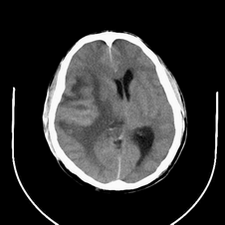

标题: CT25808:男,48岁,头痛多年,近段时间头痛加重伴步态不稳 [打印本页]

标题: CT25808:男,48岁,头痛多年,近段时间头痛加重伴步态不稳

平扫:右颞顶叶病灶呈等低密度伴大面积水肿,脑室受压变形。增强:病灶显著强化。考虑淋巴瘤或黑色素瘤。

1)不排除黑色素瘤可能;建议行mri检查。2)大脑镰下疝。3)脑积水(梗阻性)。